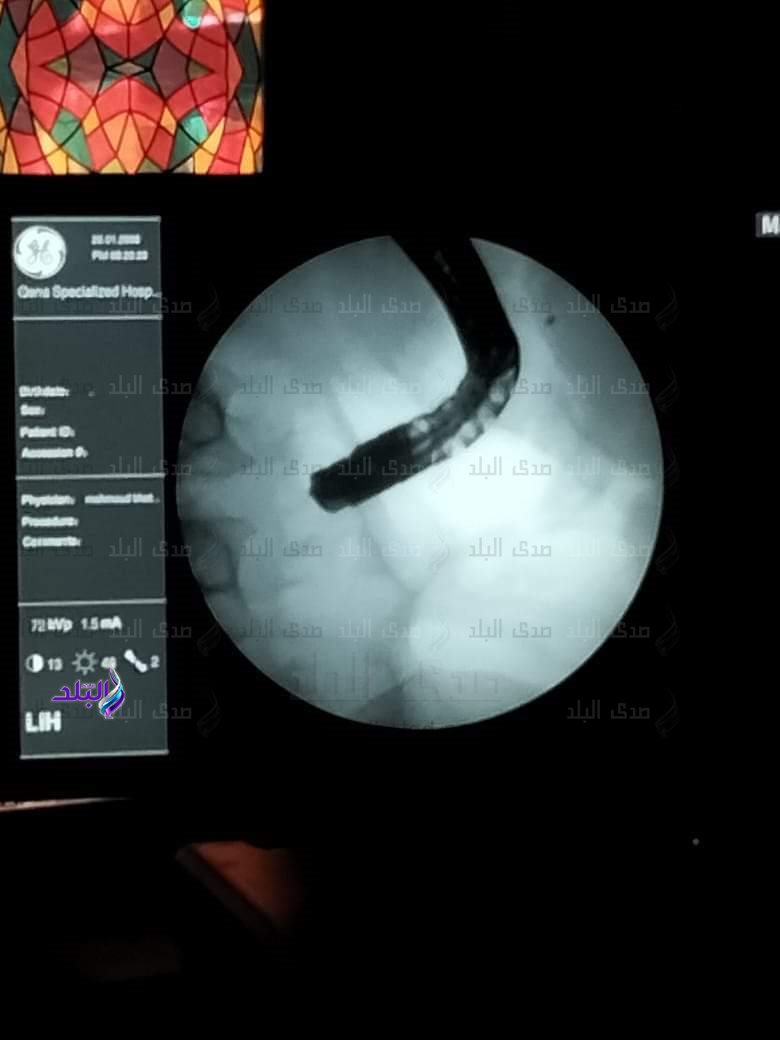

قال الدكتور راجي تاوضروس، وكيل وزارة الصحة بـ قنا ، إن فريق طبي بمستشفي حميات قنا نجح في إجراء منظار للقنوات المرارية لحالة مريض يبلغ من العمر ٥٢ عاماً كان يعاني من إنسداد بالقنوات المرارية وإرتفاع في نسبة الصفراء بالدم.

أوضح وكيل وزارة الصحة بـ قنا ، بأن الفريق الطبي تمكن من عمل توسيع بالقنوات المرارية وتركيب دعامة للحالة المرضية، مع تحسن واستقرار الحالة الصحية للمريض، ويخضع حالياً للمتابعة من قِبل الفريق الطبي بالمستشفي لحين التعافى التام.

وأضاف تاوضروس ، بأن الفريق الطبي ضم كل من: الدكتور مصطفي محمود سيد، الأستاذ بجامعة أسيوط، والدكتور شاذلي محمد علي، رئيس وحدة المناظير بحميات قنا ، والدكتور محمد حامد، أخصائي الكبد بالمستشفى.